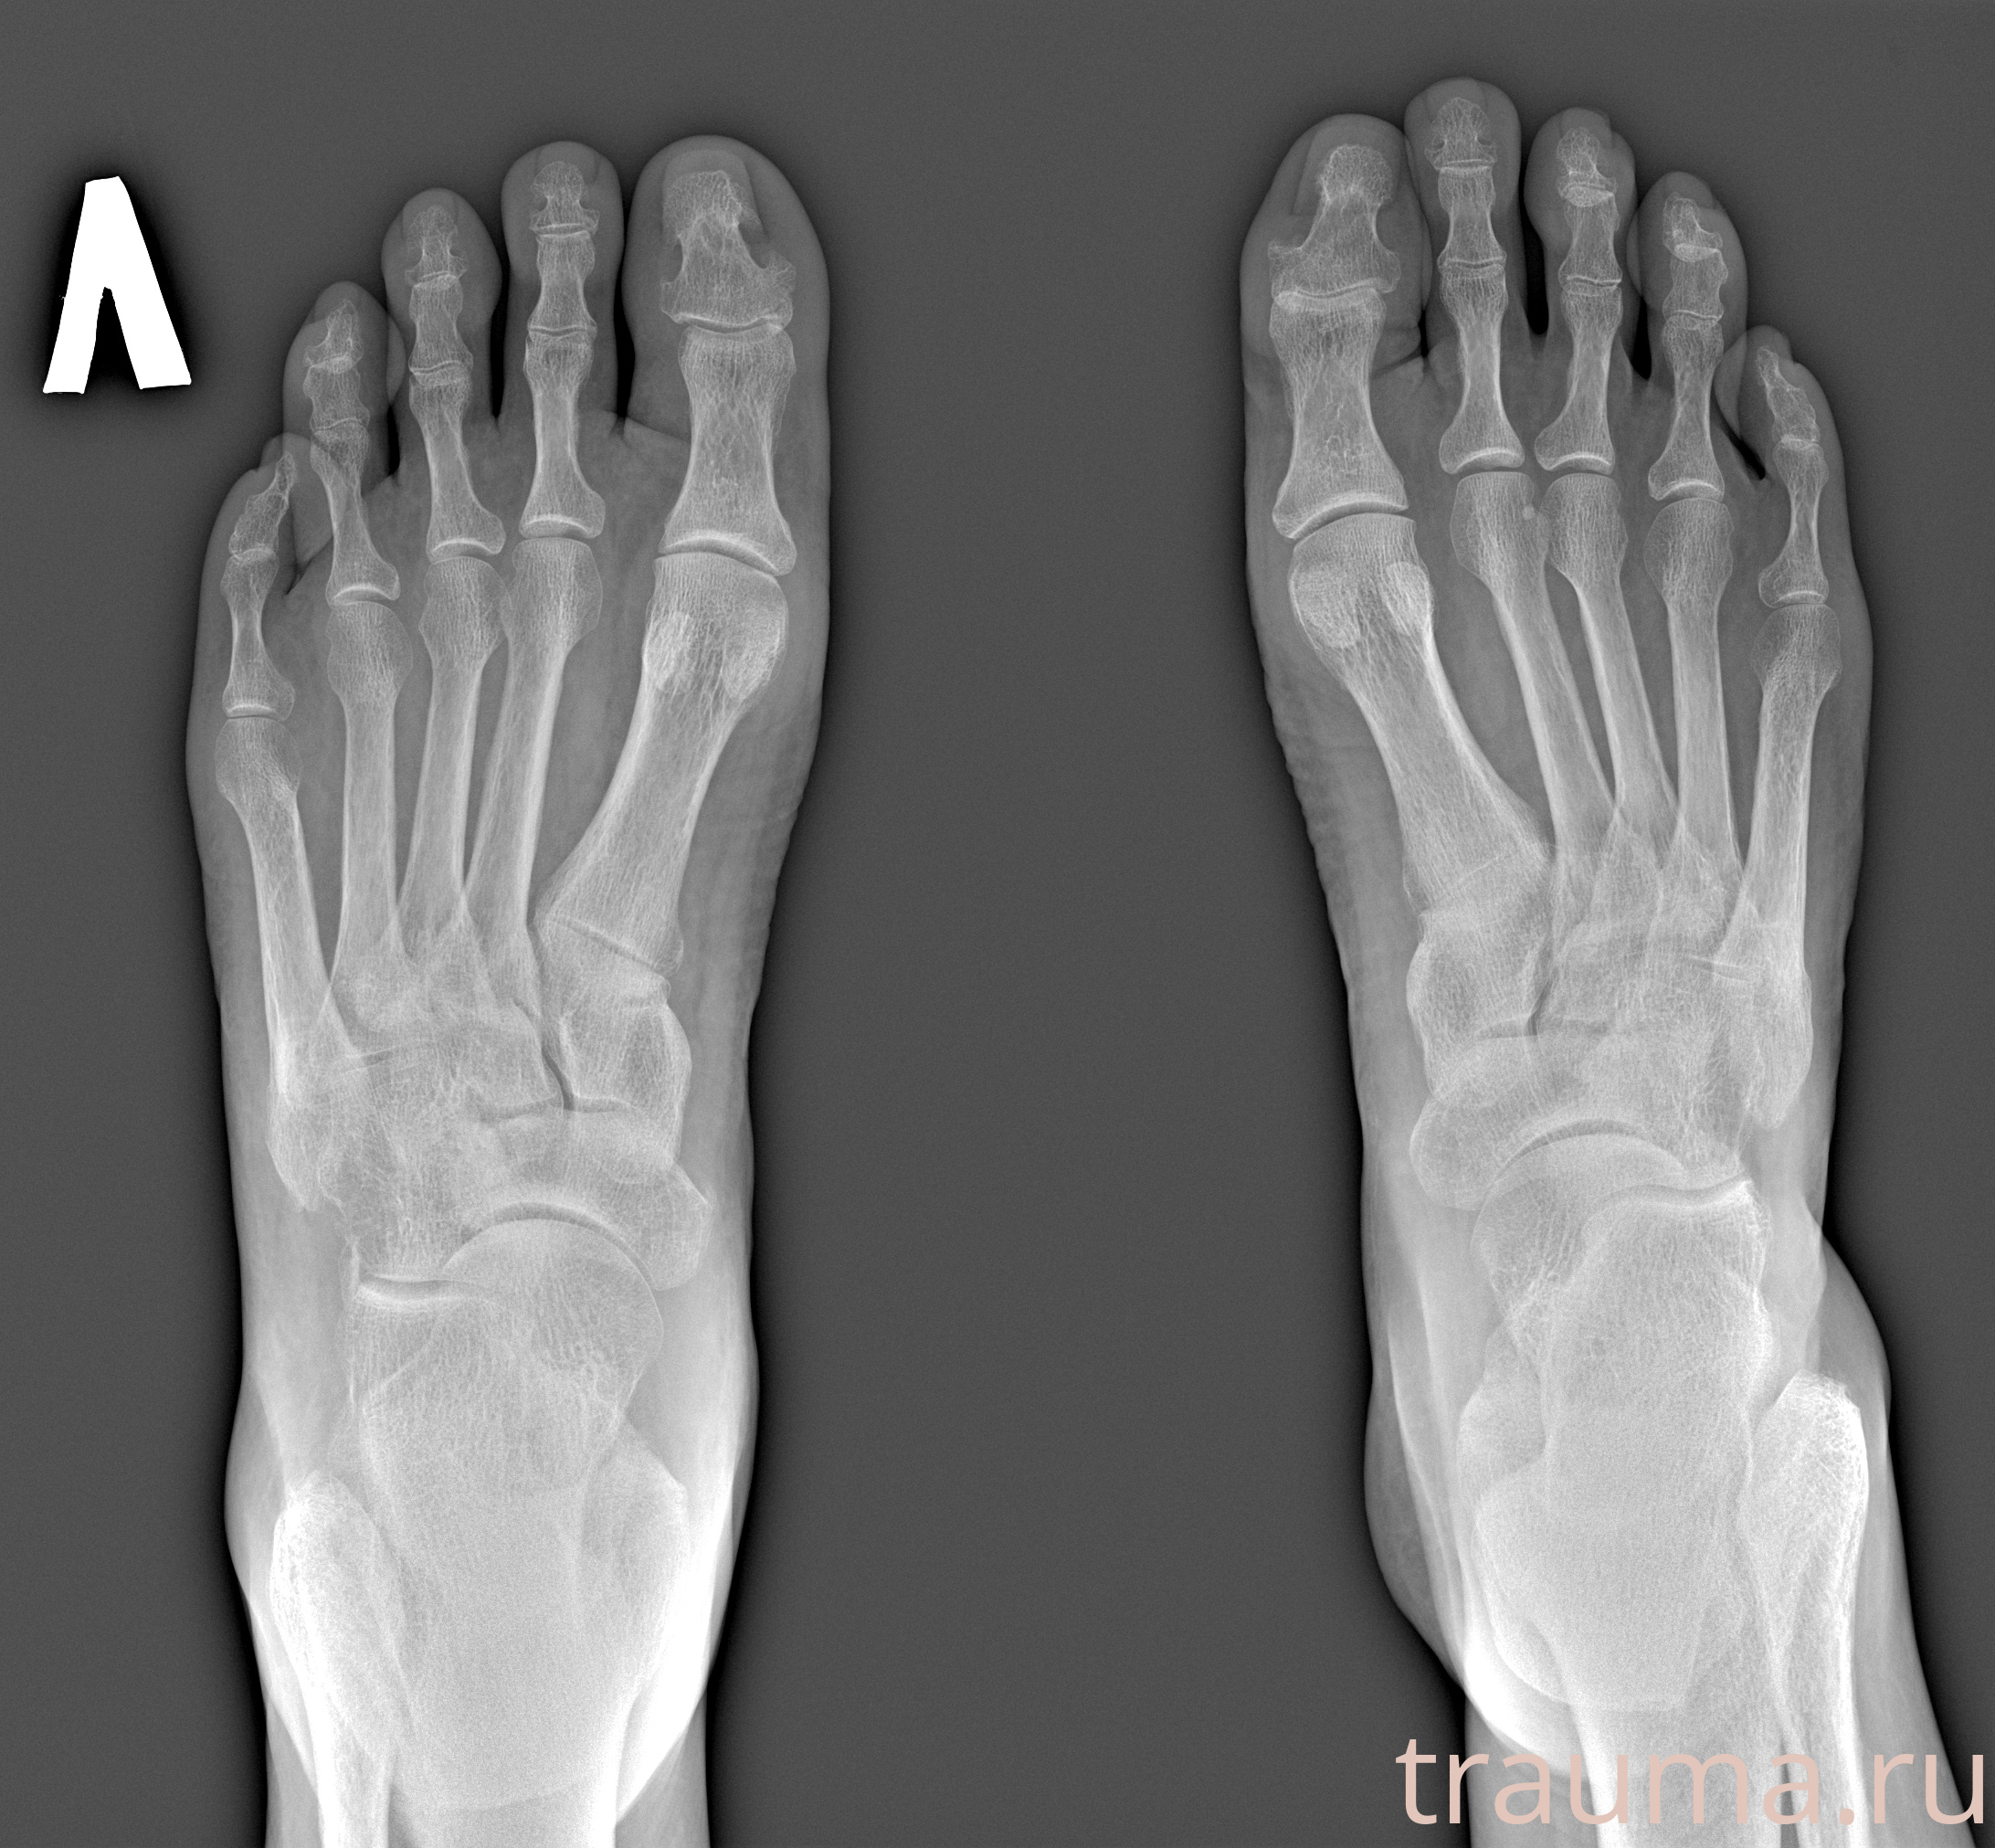

Рентгенограммы

Рентген на дому: по вашему адресу приезжает врач-рентгенолог, травматолог-ортопед с мобильным рентгеновским аппаратом, проводит диагностику травмы или заболевания, делает необходимые рентгенограммы, дает рекомендации по дальнейшему лечению. Получить качественные снимки в домашних условиях возможно благодаря уникальной методике, разработанной МосРентген Центром для института  Склифосовского